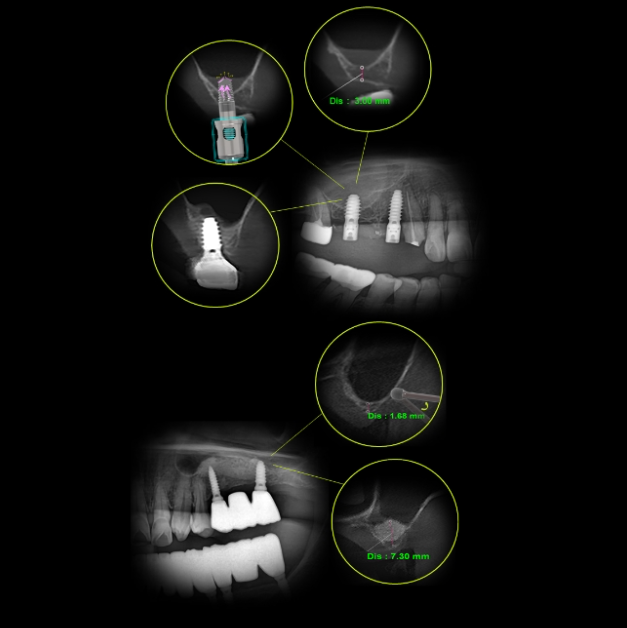

Concept 2DigitalDigital Minimalism

From Diagnosis to Treatment

High Accuracy, increased efficiency- Accuracy

Leverage advanced digital diagnostics and guided workflows for precise implant planning and placement.

Minimize errors by focusing only on processing essential information and

at each step.

- Efficiency

Streamlined, minimalist processes eliminate unnecessary steps.

Accelerate clinical workflows without sacrificing quality or outcomes.

- Patient Experience

Simplified procedures lead to less chair time and greater comfort.

Clear communication and fewer appointments enhance patient satisfaction.